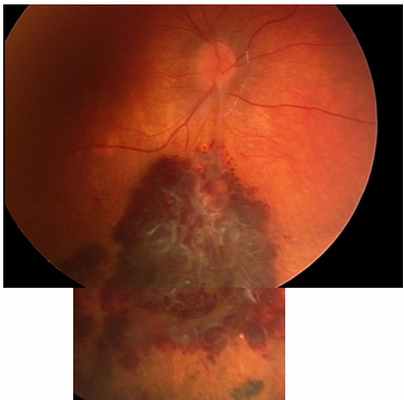

№1. Пациент К. Возраст 2,5 г. Диагноз: ОД - кавернозная гемангиома сетчатки, состояние до лечения.

Состояние через год после проведенной брахитерапии с Ru-106+Rh-106 – полная регрессия опухоли, остаточный рубцовый очаг в заинтересованной зоне.